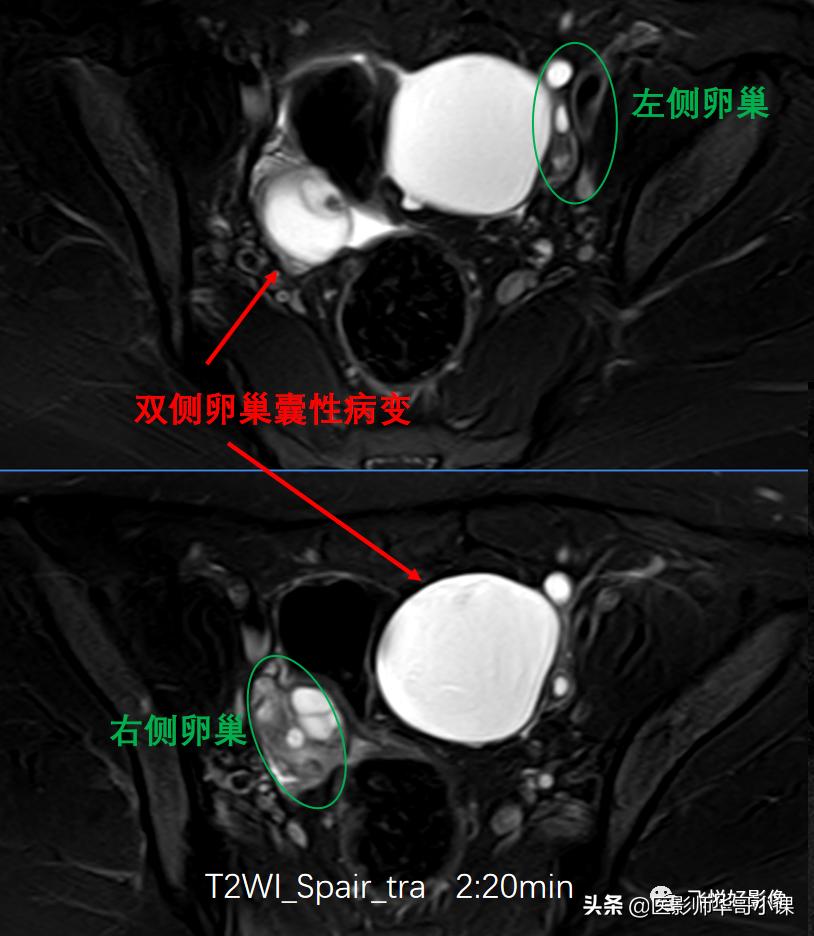

图1.T2WI_SPAIR_TRA

T2W_SPAIR横断位及冠状位图像(图1&图2)可以看到,盆腔双侧附件区见两个类圆形占位性病变,T2WI压脂高信号,边界清晰,边缘光滑,其内信号均匀,未见明确实性信号,病变与卵巢关系密切。